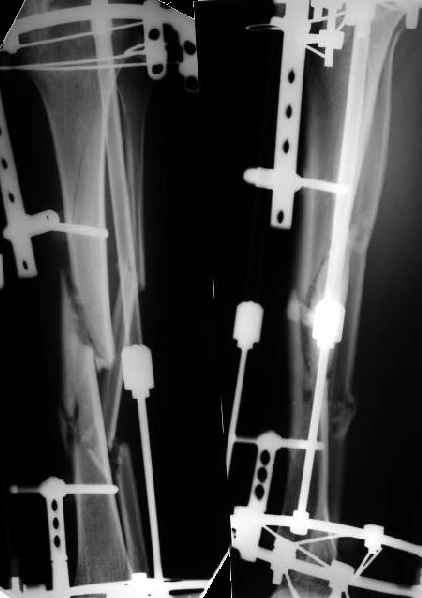

Как я уже сообщал, пациент поступил к нам в пятницу на прошлой неделе.

Ко всему прочему у него еще и разгибательная контрактура коленного сустава - амплитуда градусов 15.

Сегодня сделана операция. Из бедра минимально инвазивно удалены пластинки. Один винт на верхней пластинке оказался сломан, так что пришлось там сделать разрезик побольше, см 5.

Хотя и с трудом, но на бедре удалось сразу выполнить закрытый интрамедуллярный остеосинтез с минимальным рассверливанием.

Редрессацию колена даже пытаться делать не стали.

На голени - чрескожная остеотомия малоберцовой кости, закрытая остеоклазия большеберцовой, дистракционный остеосинтез аппаратом.

В плане - востановление длины и оси голени, разработка движеий в колене. Не уверен, что удастся синтезировать голень стержнем при таком маленьком сгибании в коленном суставе.